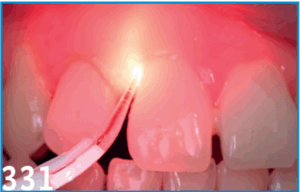

Dans la société actuelle, les standards de l’esthétique poussent de plus en plus de patients à avoir recours à des soins d’orthodontie pour restaurer leur sourire et la demande des adultes en matière d’orthodontie s’est beaucoup développée ces dernières années. Un des motifs de consultation concerne les migrations dentaires secondaires favorisées par le développement d’une maladie parodontale. Il apparait donc très important de prendre en charge la maladie parodontale avant d’entreprendre un traitement orthodontique afin d’éviter d’éventuelles complications et afin de pérenniser le résultat espéré.

L’objectif de cet article est de faire le point sur les situations à risque parodontal avant tout traitement orthodontique et de proposer un protocole de prise en charge reproductible intégrant la technologie innovante des lasers et son apport dans le traitement parodontal pré-orthodontique non chirurgical.